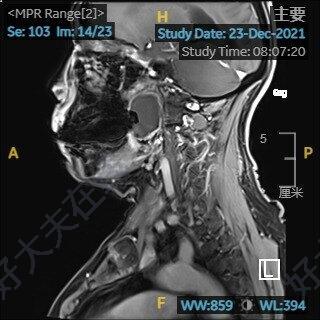

9月初,24歲女孩陳某來到華東醫(yī)院門診就診,她告訴我近10月來咽部異物感,打呼也比較厲害,最近一個月感覺說話口中有東西,也有點(diǎn)含糊不清,在他們當(dāng)?shù)蒯t(yī)院查CT咽喉有個腫物,查看了CT,發(fā)現(xiàn)其咽旁間隙有一個大約7cm4.5cm腫物,此病人所描述的咽喉腫物其實(shí)是咽旁間隙腫瘤。什么是咽旁間隙腫瘤,究竟咽旁間隙在哪里?有什么危害呢,今天我?guī)Т蠹覍W(xué)習(xí)這個部位的疾病。咽旁間隙解剖咽旁間隙是一上起顱底下至舌骨、位置深在、解剖關(guān)系復(fù)雜的潛在間隙,由頭頸部筋膜圍成,呈倒錐體形,底向顱底,尖對舌骨大角,其內(nèi)側(cè)界為咽的外側(cè)壁,鄰近鼻咽及口咽,外側(cè)界為翼突內(nèi)側(cè)板的內(nèi)側(cè)面、下頜骨升支、腮腺筋膜及部分二腹肌后腹;后界為椎前及椎旁筋膜。莖突及其附著結(jié)構(gòu)將其分為莖突前間隙和莖突后間隙,莖突前間隙包括腮腺深葉、翼肌、脂肪及淋巴等組織;莖突后間隙則包含頸動脈鞘及其內(nèi)的頸內(nèi)靜脈、頸內(nèi)動脈、Ⅸ~Ⅻ腦神經(jīng)、頸交感鏈,頸深淋巴結(jié)及脂肪等諸多重要組織結(jié)構(gòu)。咽旁間隙腫瘤咽旁間隙腫瘤是指發(fā)生在咽旁間隙的腫瘤,比較少見,僅占所有頭頸部腫瘤的0.5%[1]。一項(xiàng)對1293例[2]咽旁間隙腫瘤患者的系統(tǒng)回顧發(fā)現(xiàn),大約82%的腫瘤是良性的,18%是惡性的。常見的良性腫瘤有神經(jīng)鞘瘤和多形性腺瘤,少部分是惡性腫瘤,包括原發(fā)于咽旁間隙的惡性腫瘤和繼發(fā)性轉(zhuǎn)移癌。臨床表現(xiàn)與相關(guān)檢查良性腫瘤,由于其生長緩慢,位置潛在,故早期多無明顯癥狀,隨著病情的發(fā)展主要表現(xiàn)為頸部腫物及鄰近器官結(jié)構(gòu)受累的癥狀:患者經(jīng)常無意中或查體時(shí)發(fā)現(xiàn)頸部的無痛性腫物,如位置較高,壓迫咽鼓管,患者會出現(xiàn)耳鳴、耳悶,長期頑固性分泌性中耳炎;突向口咽部或者下咽部,堵塞氣道,患者常表現(xiàn)為口中含物、夜間明顯打呼,甚至經(jīng)常憋醒,也就像我們這個小姑娘的癥狀;如果神經(jīng)受累將出現(xiàn)相應(yīng)神經(jīng)損傷癥狀,比如迷走神經(jīng)受累會出現(xiàn)聲音嘶啞,交感神經(jīng)受累出現(xiàn)horner綜合征等。惡性腫瘤轉(zhuǎn)移繼發(fā)多見,比如鼻咽癌,下咽癌、喉癌、舌癌等頭頸惡性腫瘤淋巴結(jié)轉(zhuǎn)移,術(shù)前評估非常重要,懷疑惡性的需要做好相關(guān)檢查,包括鼻咽喉鏡排除隱匿原發(fā)病灶。CT及MRI檢查對咽旁間隙腫瘤的評估至關(guān)重要,增強(qiáng)的CT、MRI及血管造影可以評估腫瘤與周圍血管關(guān)系以及腫瘤血運(yùn)情況,對手術(shù)評估和指導(dǎo)有很大作用,MRI對于腫瘤的定位和起源的鑒別也具有重要指導(dǎo)作用。良性腫瘤:惡性轉(zhuǎn)移性腫瘤:治療方面咽旁間隙腫瘤手術(shù)風(fēng)險(xiǎn)比較大,隨著內(nèi)鏡技術(shù)的發(fā)展和患者對美容要求的提高,很多位置深在的腫瘤根據(jù)所在平面不同可以在口內(nèi)或者鼻腔內(nèi)鏡下完成,當(dāng)然,這需要做好充分的評估,由于咽旁間隙解剖結(jié)構(gòu)復(fù)雜,判斷腫瘤與周圍血管的關(guān)系非常關(guān)鍵,這需要外科手術(shù)技術(shù)嫻熟、解剖非常熟悉的耳鼻喉科醫(yī)生完成。經(jīng)頸外入路是相對最為安全和經(jīng)典的治療方式,在手術(shù)過程中可以較好顯示顱神經(jīng),控制大血管,一旦出現(xiàn)出血,可以在直視下處理;由于咽旁間隙特殊的解剖位置,雖然處理相對于其他頸部腫瘤手術(shù)較棘手,但與口內(nèi)或者鼻腔內(nèi)鏡下手術(shù)方式相比,一旦手術(shù)過程中出血,處理相對從容。陳某的咽旁間隙腫瘤比較大,最大長徑約7cm,橫徑4.5cm,在頜下區(qū)僅能摸到一點(diǎn)腫瘤下極,這么大的腫瘤手術(shù)難度相對比較大,口內(nèi)徑路一旦出血很難處理,華東醫(yī)院耳鼻喉科頭頸團(tuán)隊(duì)術(shù)前做好充分的評估,準(zhǔn)備好各種預(yù)案,順利完成手術(shù),術(shù)后一周正常出院。參考文獻(xiàn):1LimJY,ParkYM,KangMS,etal,ComparisonofSurgicalOutcomesofRoboticandConventionalApproachesinPatientswithPre-andPoststyloidParapharyngealSpaceTumors.AnnSurgOncol.2020Oct;27(11):4535-4543.2KuetML,KasbekarAV,MastersonL,etal.Managementoftumorsarisingfromtheparapharyngealspace:Asystematicreviewof1,293casesreportedover25years.Laryngoscope.2015Jun;125(6):1372-81.

治療前患者女性,83歲主訴:左側(cè)頭痛1周,磁共振發(fā)現(xiàn)左側(cè)咽旁間隙腫物3天?,F(xiàn)病史:患者1周前無明顯誘因出現(xiàn)左側(cè)顳區(qū)頭痛,呈間斷性,性質(zhì)為脹痛,無明顯時(shí)間規(guī)律。就診于當(dāng)?shù)蒯t(yī)院,頭顱MR提示:左側(cè)咽旁間隙腫物。建議上級醫(yī)院就診。治療后治療后1月腫瘤完整切除,術(shù)后病理小涎腺基底細(xì)胞腺瘤